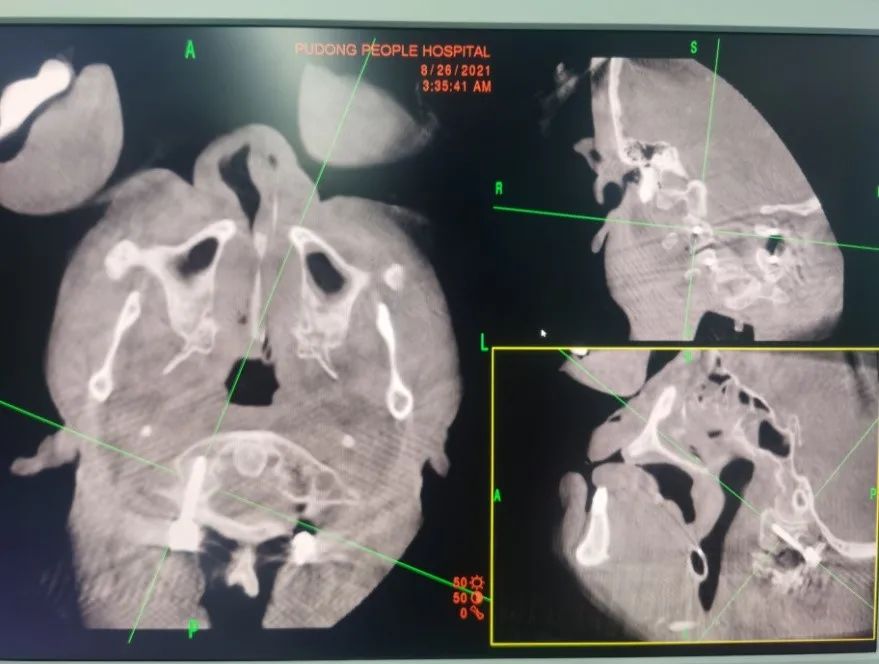

患者术前颈椎CT、MRI显示枢椎齿状突骨折伴寰枢椎后脱位

该患者属于严重的枢椎齿状突骨折合并寰枢椎后方脱位,此类型骨折脱位患者临床及其罕见,致死、致瘫率极高,手术难度大、风险高,是大多数脊柱外科医生不愿触碰的领域。急救团队待患者生命体征平稳后收入重症ICU监护治疗、并行颅骨持续牵引稳定齿状突骨折、复位寰枢椎脱位,同时脊柱外科团队接到会诊,王健主任第一时间组织讨论为患者制定了进一步的治疗方案。

术前椎动脉CTA未见椎动脉高跨表现手术方法主要以前路齿状突螺钉加压内固定术和后路内固定手术为主:前路齿状突螺钉加压内固定术相对安全,但螺钉固定强度及复位能力不足;后路内固定手术方式相对安全的有椎板夹内固定、钢丝内固定等,但同样固定强度不佳,骨折端不融合发生几率高,枕颈融合术相对固定强度较大,但颈椎活动度受到限制,患者远期效果并不理想。为让患者术后保留更多的颈椎活动范围,手术团队放弃了风险相对较低的枕-颈融合术,而采用手术技术要求极高的寰-枢椎椎弓根钉内固定手术。在决定了治疗方案后,脊柱外科团队对患者进行了一系列术前准备工作,包括颈椎MRI检查、椎动脉CTA明确有无椎动脉解剖变异等。